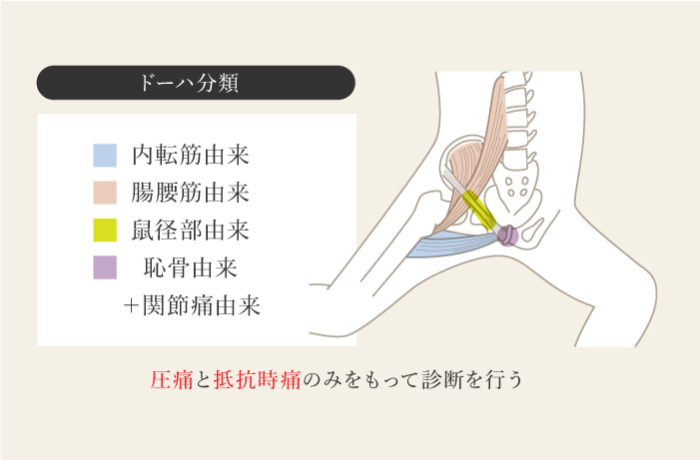

鼠径部痛症候群

グローインペイン

体幹から股関節周辺にかけての筋肉や関節の柔軟性が低下することにより、拘縮や骨盤を支える筋肉が不安定になり、体幹と下半身の動きがうまく連動しなくなった状態で無理に運動を続けていると、鼠径部から股関節にかけて痛みが発生する。キック動作を繰り返すサッカー選手に多くみられる。